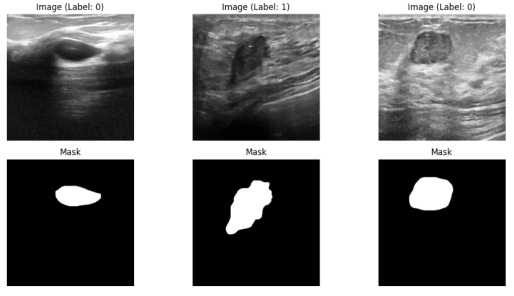

The Breast Ultrasound Images (BUSI) dataset [25] was collected at baseline from women aged 25–75 years, organized in 2018 with 780 B-mode ultrasound images (PNG format, average resolution 500 × 500 pixels) from 600 female patients. Each image is accompanied by pixel-level ground truth masks delineating lesion boundaries. The dataset comprises three classes: Normal (133 images), Benign (437 images), and Malignant (210 images), enabling both segmentation and classification tasks. Representative samples are illustrated in Figure 2.

Refer to caption

Figure 1: Representative samples from BUSI dataset.